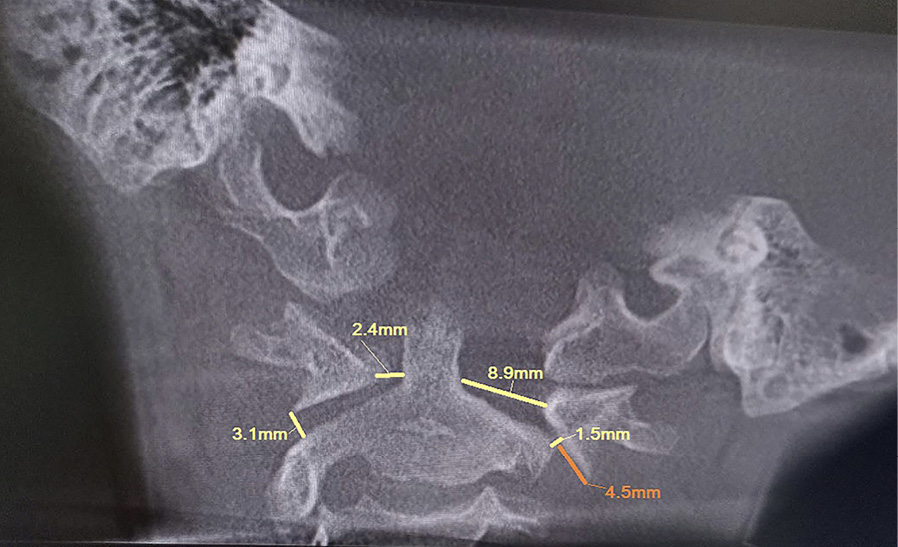

Пациент В. 9 лет обратился с жалобами на боли и вынужденное положение головы в виде наклона вправо. Из анамнеза, со слов матери, данное состояние возникло на фоне проведенной эндоскопической аденотомии и тимпаноскопии справа около 3 недель назад. На 2-е сутки после проведенного вмешательства, со слов матери, у ребенка появилось вынужденное положение головы в виде наклона вправо и постоянные боли постепенного нарастающего характера по боковой поверхности шеи справа. По данному поводу спустя 7 дней мальчик был консультирован у оперирующего хирурга, который расценил данную ситуацию как допустимые изменения послеоперационного характера. В связи с отсутствием очевидных улучшений мать ребенка приняла решение о необходимости обращения к врачу травматологу-ортопеду. При первичном осмотре ребенка отмечался вынужденный наклон головы вправо до угла в 54°, боли при пальпации по боковой поверхности шеи справа (6-7 баллов по Визуально-аналоговой шкале). Пассивные движения в шейном отделе позвоночника были представлены безболезненным наклоном вперед в пределах 10°, наклоном назад в пределах 3°, наклонами вправо и влево в пределах 5°. Активные движения в шейном отделе позвоночника были представлены в виде безболезненного наклона вперед в пределах 15°, назад в пределах 5-7°, наклонов вправо и влево в пределах 7–10 градусов. Превышение представленных объемов пассивных и активных движений вызывало усиление болей, ротационные движения осуществить не удалось. По остальным отделам костно-мышечной системы отклонения не выявлены. С учетом клинической картины было принято решение выполнить КЛКТ, по результатам которой зафиксировано следующее: ротация атланта вправо вокруг вертикальной оси без передней дислокации. Рентгеновская щель срединного атлантоаксиального сустава не расширена, равна 2,5 мм, что соответствует возрастной норме. Суставные рентгеновские щели латеральных атлантоаксиальных суставов асимметричны: справа 3,1 мм, слева 1,5 мм. Расстояние между медиальными краями боковых масс атланта и зубом аксиса: справа – 2,4 мм, слева – 8,9 мм (рис. 1). Определяется боковое смещение атланта влево: нижняя суставная поверхность левой боковой массы атланта смещена на 4,5 мм влево относительно суставной поверхности аксиса.

Рис. 1. Конусно-лучевая компьютерная томография краниовертебральной области, фронтальный срез на уровне зубовидного отростка С2 позвонка. Методика измерения соотношений в латеральных атланто-аксиальных суставах